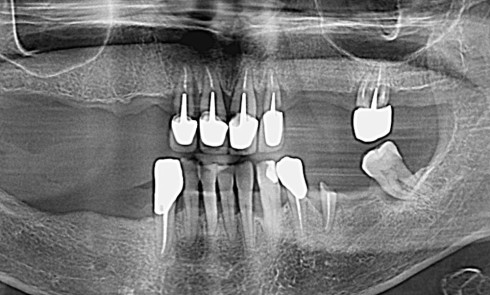

Quelles sont les spécificités de la pressée sur zircone ? Quelle est sa mise en oeuvre ? Comment analyser les échecs pour une fiabilité à longue échéance ?

Le traitement implanto-prothétique des édentements complets mandibulaires en présence de résorptions sévères représente un défi chirurgical et prothétique majeur. Cet article...